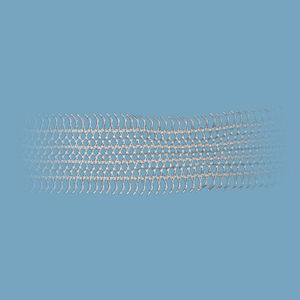

banda de reconstrucción para la incontinencia urinariaInGyne S

... Sistema protésico Uro-ginecologíco compuesto por una banda/sling de polipropileno monofilamento y los introductores desechables de acero inoxidable requeridos. Indicaciones: Tratamiento dela incontinencia femenina por stress urinario Embalaje: ...